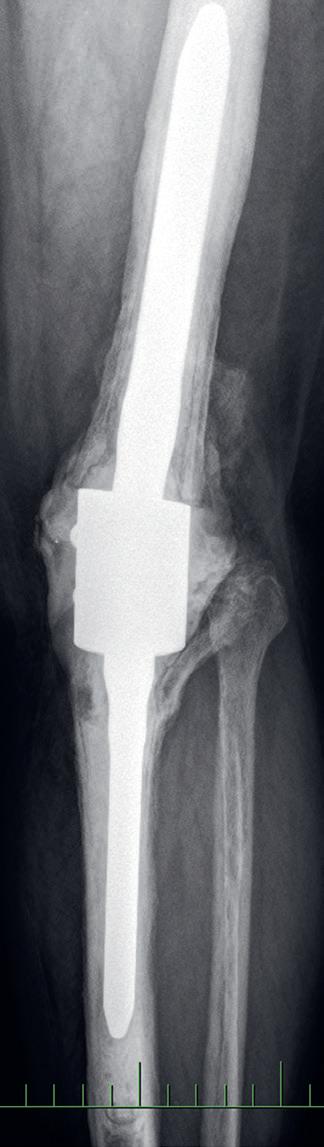

Osteotomie má za cíl korekci kloubní osy se změnou zátěžových oblastí kloubu. Operace obnoví osu končetiny a odlehčí tlak na poškozenou oblast kloubu a zmírní tak subjektivní obtíže nemocného. Příznivý výsledek obvykle přetrvává několik let. Dle poruchy osy rozlišujeme osteomie valgizační (korekce genu varum) a varizační (korekce genu valgum). V praxi se provádí klínovitá osteotomie s vytětím kostního klínu, sesazením obou fragmentů a fixací osteosyntézou (tzv. closed wedge osteotomie, obr. 19.5). Druhou možností je provedení jednoduché osteotomie s rozevřením obou fragmentů v klínovitém tvaru a fixace osteosyntézou (tzv. open wedge osteotomie, obr. 19.6). Dále podle anatomické lokality osteotomie rozlišujeme osteotomie distálního femuru (obr. 19.7) nebo proximální tibie. Artrodéza (ztužení kloubu) se primárně používá ve výjimečných případech (obr. 19.8). Je však možným řešením zejména po selhání aloplastiky, pokud není možná implantace nové náhrady. Vzhledem k faktu, že ztužení kloubu probíhá obvykle v terénu rozsáhlých kostních ztrát, používá se v poslední době ztužení kloubu pomocí implantátů – tzv. fúze kolenního kloubu (obr. 19.9). Nejde tedy v pravém slova smyslu o klasickou artrodézu – tedy kompletní primární kostní srůst femuru a tibie.

Obr. 19.8: Artrodéza kolenního kloubu – patrný srůst resekovaných kloubních ploch femuru a tibie v AP (a) a bočné (b) projekci

Obr. 19.9: Rentgenový snímek fúze kolenního kloubu pomocí implantátu v AP (a) a bočné (b) projekci